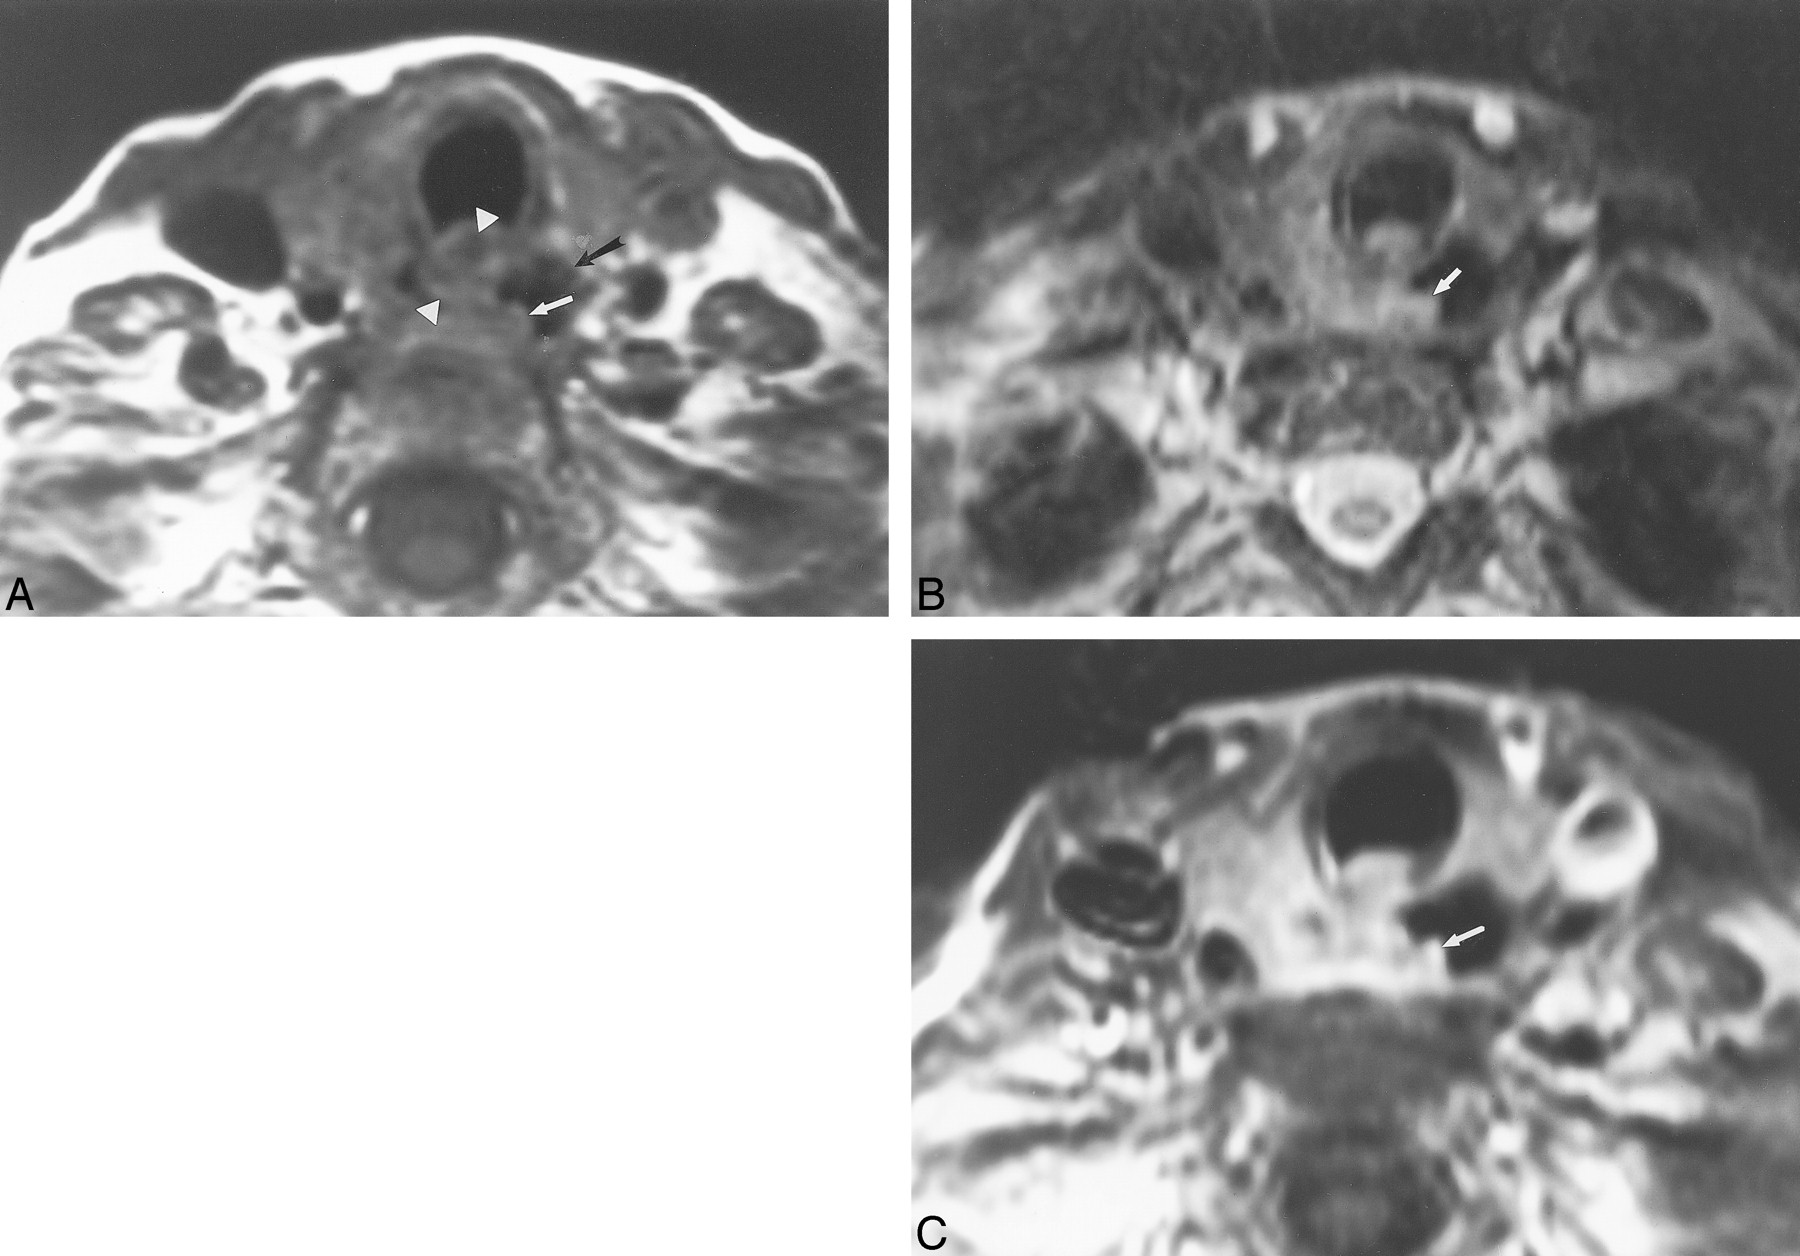

MR imaging is more accurate at predicting the lack of EI rather than its presence (Fig 4). Perhaps the use of oral contrast for MR imaging (11, 30) may improve specificity for detecting esophageal invasion. Although there is no single perfect MR criterion, the combination of the various criteria with the higher accuracies listed above are recommended for predicting EI. This is important for surgical planning in cases that may require complex esophageal resections and reconstructions.

This 72-year-old woman had follicular carcinoma of the left lobe of the thyroid. This case represents a false-positive interpretation of esophageal invasion. There was no evidence of esophageal invasion by surgical or pathologic evaluation.

A, Axial T1-weighted image (700/17) shows effacement of the fat plane between the esophagus and the left thyroid (arrow).

B, Axial T2-weighted image (3000/78) shows focal increased signal within the esophageal wall adjacent to the thyroid mass (arrowheads) compared with the normal right lateral wall of the esophagus (arrow).